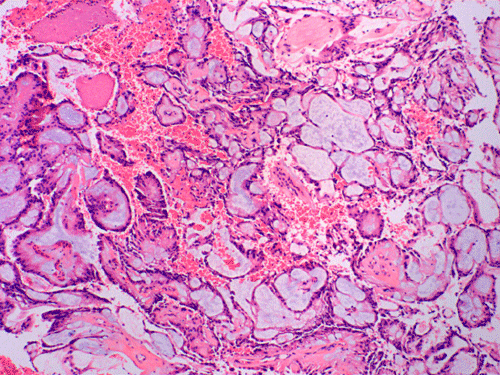

On cytologic preparations, there are clumps of tissue that do not smear out well (Panel A). On higher magnification, these tissue clusters are composed of large blobs of bluish, acellular, mucoid material admixed with cells with relatively uniform, bland nuclei and small amount of cytoplasm (Panel B). In the less tightly packed areas, the long cytoplasmic processes of the cells can be well appreciated (Panel C). These long processes are highly suggestive of a glial neoplasm. On frozen sections, the lesion is composed of multiple blobs of bluish, mucoid material surrounded by tumor cells (Panel D and E). Features of the paraffin sections are not that much different from that of the frozen sections (Panel F G H).

Histopathology: The salient feature of myxopapillary ependymomas is a rich, thin walled micropapillary bundle surrounded by a single of epithelium that varies from low cuboidal to columnar. The cells typically have rounded nuclei with a delicate, rather open chromatin and a moderate amount of amphophilic cytoplasm. The cores of the papillae consist of blood vessels surrounded by a variable amount of mucinous matrix. The amount varies from small to substantial. The vessels are characterized by extensive thickening and hyalinization of the vessel wall. Ins some tumors, there are components with features of conventional ependymomas 24. Mitotic activity is very low or absent 25. Myxopapillary ependymomas usually have sharply defined margins, although nerve roots may be enclosed. A proportion of tumors are surrounded by a condensed connective tissue capsule 11.